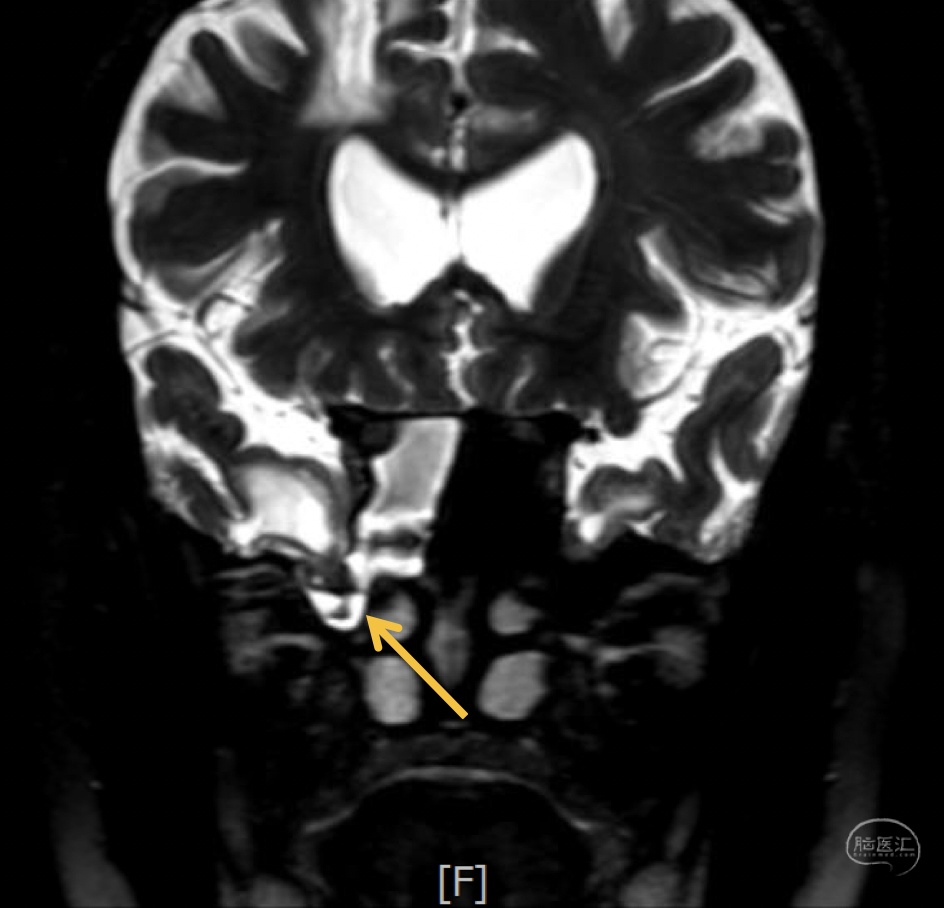

第一次术前MRI-松果体区占位,幕上脑室扩张明显,第三脑室底下疝入鞍内,蝶鞍扩大

第一次术前MRI-松果体区占位,幕上脑室扩张明显,第三脑室底下疝入鞍内,蝶鞍扩大

诊断:右侧蝶窦外侧隐窝脑膜脑膨出伴脑脊液漏。

病因分析:患者蝶窦过度气化,一直延伸至翼突,形成蝶窦外侧隐窝,造成中颅窝底出现薄弱区。患者第一次手术前因为松果体肿瘤,造成严重脑积水,颅内压明显增高,促使脑膜脑组织自颅底薄弱区疝出。但第一次手术术前并无脑脊液漏,而术后才出现脑脊液漏,可能的原因是:术前脑积水,造成颅内压较高,增高的颅内压一方面促使脑膜脑膨出,另一方面也迫使脑组织堵塞住了漏口,因而未出现脑脊液漏,手术后肿瘤全切除,脑积水缓解,颅内压下降,使得脑组织的堵塞漏口的作用下降,因此反而出现了脑脊液漏。